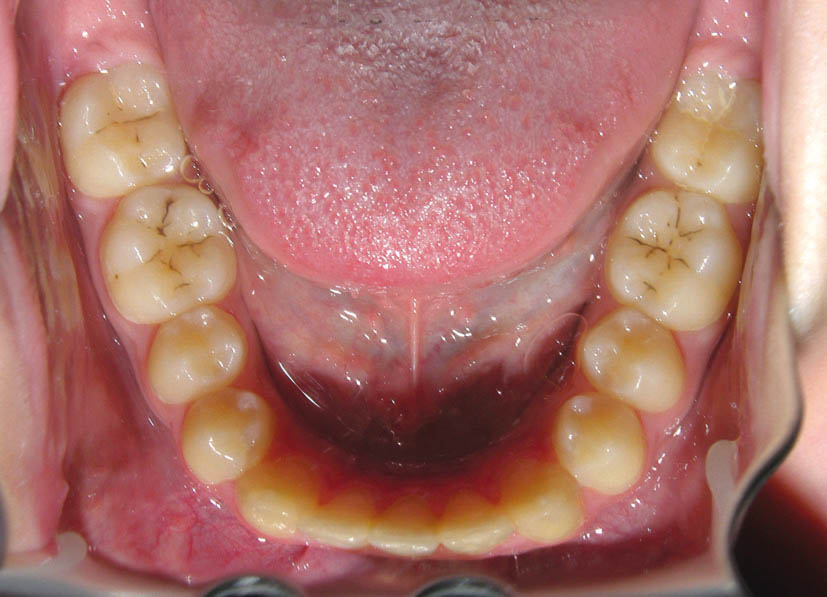

شکل 93-2: مرتب بودن دندانهای قوس بالا

شکل 96-2:کرادینگ شدید قوس بالا

شکل 97-2: مرتب بودن دندانهای قوس پایین و طرح درمان غیر کشیدنی آن